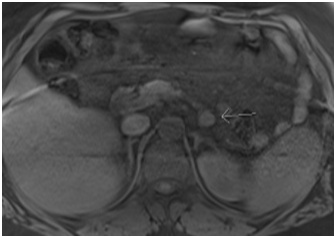

Our patient is a 42-year old morbidly obese man who underwent biliopancreatic diversion, and after losing twenty kilograms of body weight four months later, he started to have repeated episodes of severe hypoglycemia almost always induced by fasting with confirmed low blood sugar levels as low as 1.6 mmol/liter (NL 3.9–6.1) with a history of loss of consciousness several times. Two weeks before he underwent management, his hypoglycemia was persistent and he needed to be admitted to the hospital. He received continuous intravenous 10% dextrose to maintain his blood sugar just above 4 mmol/liter. His physical examination was unremarkable apart from morbid obesity with a BMI of 51 kg/m2. His laboratory workup after stopping his intravenous dextrose for five minutes showed the following: blood sugar 2 mmol/liter (NL 3.9-6.1), insulin 157 pmol/liter (NL 43-193), C-Peptide 2521 pm/liter (NL 260-1390), proinsulin 1100 pmol/liter (NL 3-20). Screenings for serum sulfonylurea and meglitinides were negative. His remaining blood work included the following: AM cortisol 282 nmol/liter (NL 138-635) and kidney and liver function tests were all within normal limits. Based on these findings, we confirmed that the hypoglycemia was caused by inappropriate over secretion of endogenous insulin, and a MRI of the abdomen was performed (Figure 1), which showed a 2x1.6 cm tumor at the body of the pancreas. The patient underwent a laparoscopic partial pancreatectomy and his blood sugar normalized within minutes postoperatively. The pathological examination of the tumor revealed a 1.5 cm low grade islet cell neoplasm consistent with insulinoma (Figure 2).

Figure 1 MRI: tumor at the body of pancreas.